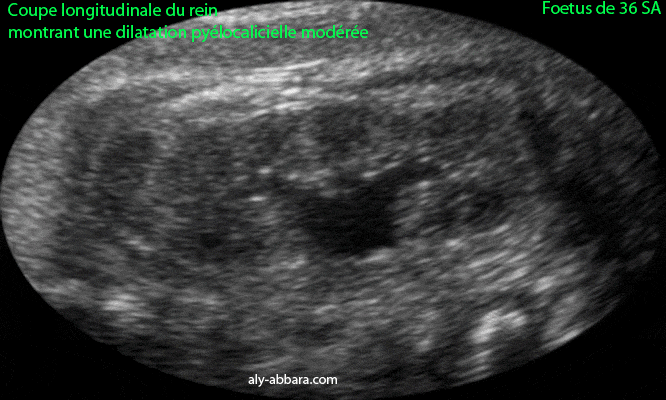

Dilatation pyéllocalicielle modérée d'un rein

Fœtus âgé de 36 SA

Coupe échographique longitudinale du rein fœtal montrant l'aspect ultrasonore de la dilatation modérée, pyélique (du bassinet) et des calices rénales .

Dans le cas présent, il s'agit d'une pyélectasie modérée bilatérale et isolée.